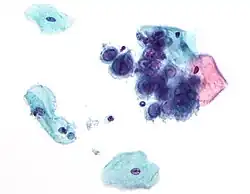

Existem mais de 30 diferentes tipos de bactérias, vírus e parasitas que podem ser transmitidos por via sexual.[1] Entre as IST causadas por bactérias estão a infeção por clamídia, gonorreia ou sífilis.[1][9] Entre as IST virais estão o herpes genital, VIH/SIDA e verrugas genitais.[1] Entre as IST causadas por parasitas está a tricomoníase.[1][10] Embora sejam geralmente transmitidas durante uma relação sexual, algumas IST podem também ser transmitidas por via não sexual, como contacto com os tecidos ou sangue da pessoa infetada, através da amamentação ou durante o parto.[1] Embora nos países desenvolvidos estejam amplamente disponíveis exames de diagnóstico, isto nem sempre é o caso nos países em vias de desenvolvimento.[1]

Vários tipos de agentes infecciosos (vírus, fungos, bactérias e parasitas) estão envolvidos na contaminação por IST, gerando diferentes sintomas como feridas, corrimentos, dor ao urinar, bolhas ou verrugas.[16]